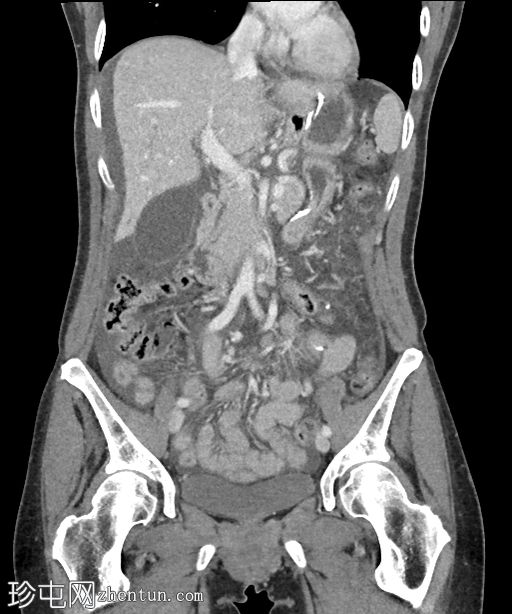

冠状位增强扫描(门静脉期)

大量游离液体和游离气体。游离气体回流至邻近的胃空肠吻合口,伴有肠壁缺损和小肠壁增厚。

漩涡征和肠系膜静脉淤血。左下腹和盆腔内可见肠壁增厚但强化的小肠袢。